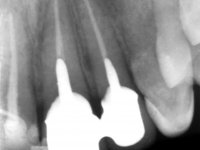

Paciente do sexo masculino, com 29 anos não fumador. Após atendimento hospitalar, na sequência de um traumatismo facial, surgiu na consulta com os dentes 2.1 e 2.2 com extensas fraturas coronais e com exposição pulpar. As fraturas eram justa-ósseas a nível palatino e as raízes apresentavam mobilidade acentuada. Os dentes 1.3,1.2 e 1.1 apresentavam-se ferulizados com um arame ortodôntico. A ferulização abrangia as superfícies vestibulares e palatinas. Os três dentes em conjunto também apresentavam mobilidade. O lábio inferior apresentava-se ainda suturado e a higiene oral era sofrível.

A –Plano de Tratamento Conservador: Realização de tratamento endodôntico nos dentes 2.1 e 2.2. Gengivectomia acompanhada ou não de osteoplastia na zona palatina dos dentes 2.1 e 2.2. Colocação de ponte provisória realizada em laboratório e confeção de espigões falsos cotos E.F.C fundidos, nos dentes fraturados. Colocação de ponte de 2 elementos com infraestrutura em Zr e cerâmica.

Foi feito o tratamento endodôntico dos dentes 2.1 e 2.2.de imediato, a sintomatologia que o paciente manifestava a isso impunha. Na mesma consulta foi realizada uma extensa gengivetomia com o bisturi elétrico, no sentido de expor os limites cervicais da fratura. Foram colocadas resinas compostas nos remanescentes radiculares com a intenção de reformular a emergência dos tecidos moles. Realizei a impressão dos remanescentes radiculares para confeção em laboratório de uma ponte provisória. A ponte provisória de 2 elementos, apresentava um formato que visava no futuro acomodar o coto dos espigões falsos cotos que iria ser cimentados nos remanescentes radiculares. Apresentava um reforço metálico palatino e dois apoios para os dentes adjacentes, um mesial e outro distal. Os remanescentes radiculares foram preparados para a confeção de dois espigões falso coto fundidos. As linhas de acabamento cervical foram definidas e os canais radiculares desobturados e preparados. A impressão foi realizada com a utilização de tutores de plástico com a técnica de dupla mistura. O afastamento gengival foi feito utilizando pasta de caolino. A ponte provisória foi rebasada em boca com acrílico auto polimerizavel, cimentada provisoriamente sobre as raízes e os apoios colados aos dentes adjacentes. No laboratório foram confecionados os E.F.C. fundidos, tendo o cuidado de preservar espaço para a definição no re preparo dentário da linha de acabamento cervical. Removida a ponte provisória foi feita a cimentação dos E.F.C. fundidos com cimento de ionómero de vidro reforçado com resina. A ponte provisória teve que ser retocada para permitir a acomodação dos cotos e simultaneamente foi readaptada à redefinida linha de acabamento cervical. Durante 2 meses a ponte provisória acompanhou a estabilização periodontal das raízes traumatizadas e simultaneamente conseguiu a maturação da arquitetura gengival.